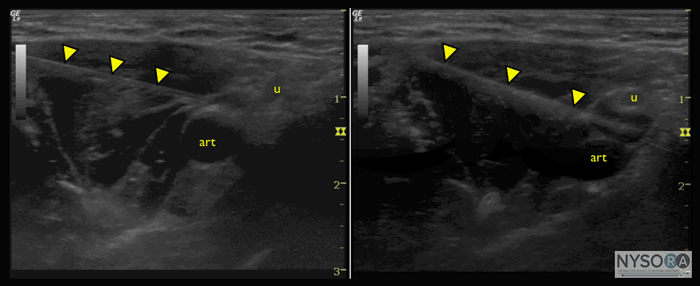

Figure 3: Axillary block with axillary artery (art), ulnar nerve (u), needle (arrowheads), (A) before and (B) after injection of small amount of local anesthetic, showing spread of injectate between artery and nerve. Injection Pressure Monitoring How, then, can the clinician distinguish the intrafascicular versus the extrafascicular needle tip placement, if ultrasound guidance is insufficient? An additional modality to ultrasound and nerve stimulation is monitoring of injection pressures. In a study of intraneural injections in dog sciatic nerves, a slow injection of lidocaine while the needle tip was intrafascicular was associated with an immediate and substantial rise in the pressure of the syringe-tubing-needle system (>20 psi), followed by return of the pressure tracing to normal (i.e., ![]() Figure 4: Inline pressure manometer with graded markings on the side (B-smart, Concert Medical, Needham, MA). The use of "hand feel" to avoid high injection pressure is unfortunately not reliable. Studies of experienced practitioners blinded to the injection pressure and asked to perform a mock injection using standard equipment reveals wide variations in applied pressure, some grossly exceeding the established thresholds for safety. (27) Similarly, anesthesiologists perform poorly when asked to distinguish between intraneural injection and injection into other tissues such as muscle or tendon in an animal model. (28) It is therefore important to use an objective and quantifiable method of gauging injection pressure. Although the practice of injection pressure monitoring during peripheral nerve blocks is relatively young, monitoring options do exist. Tsui et al described a method of "compressed air injection technique" where 10 mL of air was drawn into the syringe along with the local anesthetic. (29) Holding the syringe upright, it is then possible to avoid exceeding a maximum threshold of 1 atmosphere (or approximately 15 psi) by only allowing the gas portion of the syringe contents to compress to half of its original volume, or 5 mL. This makes use of Boyle's law, which states that pressure times volume must be constant. A pressure Another option is disposable pressure manometers specifically manufactured for this purpose. These devices bridge the syringe and needle tubing, and via a spring-loaded piston, allow the clinician to gauge the pressure in the system continuously. On the shaft of the piston are markings delineating three different pressure thresholds:20 psi (Figure 4). An advantage of this method is the ease with which an untrained assistant who is performing the injection can read and communicate the pressures. In addition, the syringe does not have to be held upright, as in the compressed air technique. Pressure monitoring may be a useful safety monitor for other aspects of peripheral nerve blocks. In a study of patients receiving lumbar plexus blocks randomized to low (20 psi) pressures, Gadsden et al demonstrated that 60% of patients in the high-pressure group experienced a bilateral epidural block. (30) Furthermore, 50% in the same group reported an epidural block in the thoracic distribution. No patient in the low-pressure group experienced bilateral or epidural blockade. This has now become an important adjunct to lumbar plexus blockade in our institution, to avoid this potentially dangerous complication.